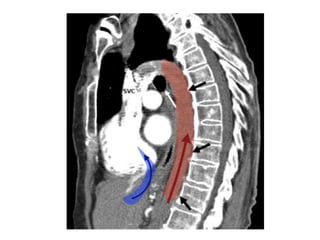

Anatomical background

Why choosing IVC?

• i.v.c physiology: